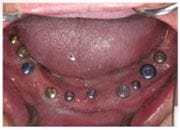

植牙過程

植入植體